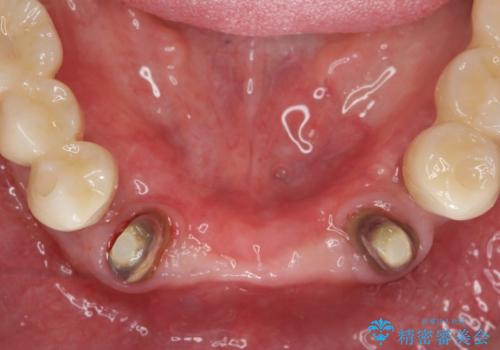

残すことのできない歯を抜去し、入れ歯になることを回避すべくブリッジ治療を行いますが支台となる歯の歯周病を改善すべく歯周病により溶けた歯槽骨の再生治療を計画します。

再生治療により良好な歯槽骨の再生が得られ、入れ歯ではなく取り外しの必要のないブリッジによる機能回復を行うことができました。